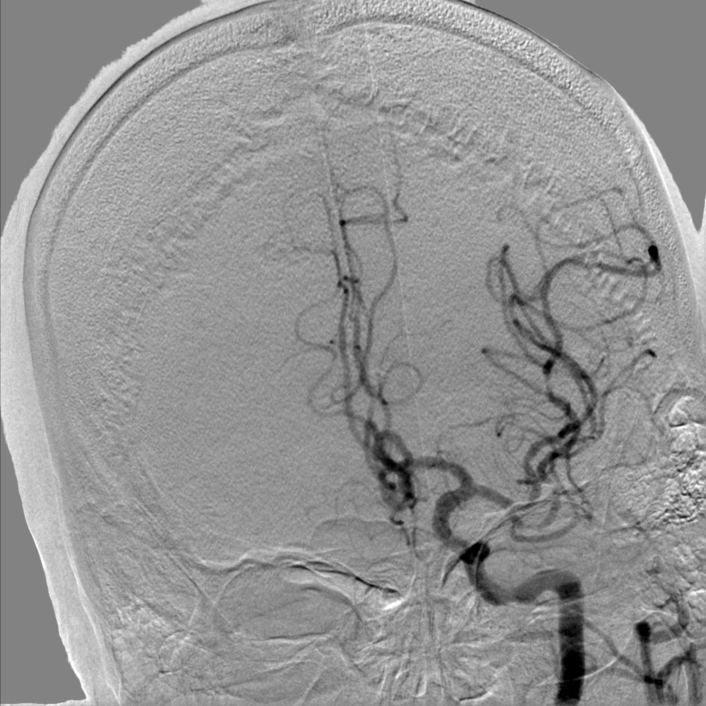

2022-10-11我院头颈DSA:

➤ 主动脉弓造影:Ⅰ型主动脉弓,右侧锁骨下动脉迂曲。

➤ 左侧颈内动脉造影:左侧颈内动脉C1段局限性狭窄约90%,C4-6段斑块形成,左侧大脑中动脉下干M2段狭窄约50%。

➤ 右侧颈内动脉造影:右侧颈内动脉C4段局限性膨大,溃疡斑块形成,C5段狭窄约50%。